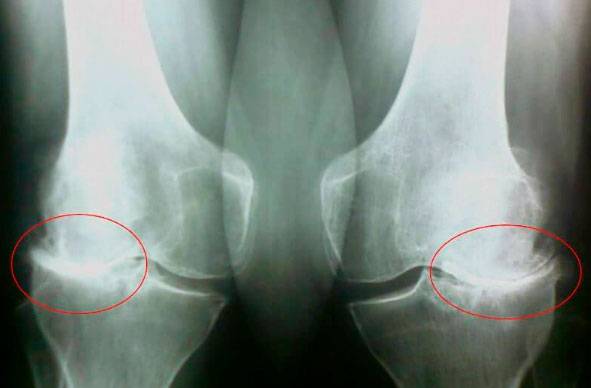

Бу суратларга қаранг, ўнг суратда бўғим оралиғи йўқ, суяклар бир-бирига ишқаланиб, қаттиқ оғриқ чақиради. Одам икки йилдаёқ ногиронга айланади.